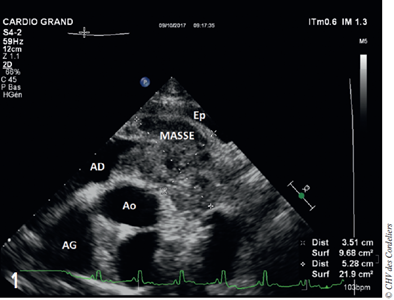

Une échocardiographie de contrôle 24 heures plus tard confirme l’absence de recollection de l’épanchement. Elle met en évidence une masse volumineuse et hétérogène, de 3,5 cm sur 5,3 cm, localisée sur la paroi atriale et auriculaire droite, avec une extension pédiculée dans l’atrium droit (fig. 1).

figure 1

Fig. 1 – Image échocardiographique de la masse (coupe parasternale droite petit axe trans-aortique).

Ep : épanchement péricardique résiduel, AD : atrium droit, Ao : Aorte, AG : atrium gauche.

Une masse de 3,5 cm sur 5,3 cm adhérente à la paroi de l’atrium et de l’auricule droit est visualisée